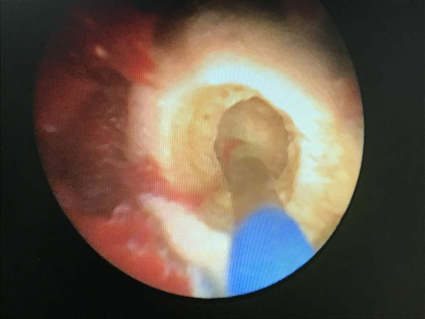

近日,我院泌尿外科常規(guī)開展經(jīng)輸尿管鏡鈥激光碎石手術,成功為一位“前列腺增生合并膀胱結石”高齡患者采用微創(chuàng)經(jīng)尿道鈥激光膀胱結石碎石、經(jīng)尿道前列腺電切手術。

患者黃老伯今年已80歲,身體條件較差,高齡且合并有“高血壓病、冠狀動脈性心臟病、腦梗塞、腦梗塞后遺癥、2型糖尿病”等,因前列腺增生合并膀胱結石,長期留置導尿,到多家醫(yī)院就診,都因患者身體狀況不佳,手術風險性較高,前列腺增生合并膀胱結石,且膀胱結石較大,故均不敢輕易手術,患者只能長期留置導尿近半年之久,對患者生活影響較大。2月中旬,黃老伯因患者長期導尿管,出現(xiàn)泌尿道感染、左側附睪炎等并發(fā)癥就診于我院泌尿外科??紤]患者的特殊性,結合近期我院泌尿外科引進了國際最先進、被譽為“碎石之星”的知名品牌鈥激光碎石機,經(jīng)充分準備,患者膀胱結石于近日成功在腰麻下行“經(jīng)尿道輸尿管鏡鈥激光膀胱結石碎石術”,在鈥激光面前結石最終化為細石塊及粉末,成功的排出了體外。碎石后同時在微創(chuàng)下并行“經(jīng)尿道前列腺電切術”,因此避免了開放手術,大大減少了手術創(chuàng)傷及手術風險,從而解決了黃老伯長久以來的困擾。目前,患者黃老伯經(jīng)復查膀胱結石已清除,拔除導尿管后排尿良好,已痊愈出院。

經(jīng)輸尿管鏡鈥激光碎石術可對任何部位的輸尿管結石、腎結石均可進行有效碎石,并可同時治療合并的尿路腫瘤、輸尿管息肉,還可微創(chuàng)經(jīng)皮輸尿管腎鏡鈥激光對腎結石進行碎石,治療膀胱結石更是易如反掌,只需通過膀胱鏡的工作通道將鈥激光光纖引入,然后發(fā)射激光,數(shù)秒鐘后結石就被擊碎并通過尿道排出,既安全又省時。過去由于醫(yī)療技術水平的限制,對于藥物和體外震波治療效果不好的患者,一般采用開放手術取石,給患者帶來了較大的創(chuàng)傷。而現(xiàn)在尿路結石的治療方法得到了迅速發(fā)展,95%以上的尿路結石可采取腔鏡下鈥激光或氣壓彈道碎石,不必采用傳統(tǒng)的開放手術治療術。鈥激光對結石的碎石作用主要依靠熱效應,可粉碎各種成分和密度的結石,其組織穿透深度<0.5mm,組織損傷輕微,術后不會因疤痕形成導致尿路狹窄,沒有穿孔、出血的危險,因此鈥激光結合內(nèi)鏡對泌尿系統(tǒng)結石具有獨特的碎石效果。目前腔鏡配合鈥激光碎石已成為治療泌尿系結石的一種重要手段。